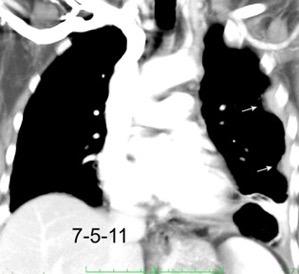

Carcinoma de mama con derrame pleural e implantes metastáticos

Makis W et al. Spectrum of Malignant Pleural and Pericardial Disease on FDG PET/CT. AJR. 2012